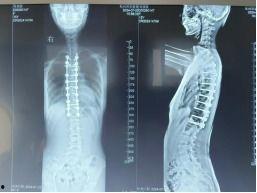

首先,让我们来了解一下脊柱侧弯。脊柱侧弯是一种常见的脊柱畸形,主要表现为脊柱向一侧弯曲。这种疾病不仅影响患者的体型,还可能引发疼痛、呼吸不畅等一系列问题。据统计,全球约有3%的人患有脊柱侧弯。

手术开始了,医生首先在女孩的背部切开一个小口,然后插入一根细长的金属棒。这根金属棒将贯穿整个脊柱,起到支撑和矫正的作用。接下来,医生在金属棒的两侧分别安装了两个金属钩,将它们固定在女孩的脊椎骨上。

随后,医生开始调整金属钩的位置,使脊柱恢复到正常状态。这一过程需要精确的操作,因为任何一点偏差都可能导致手术失败。经过一番努力,医生终于将脊柱矫正到理想的位置。

接下来,医生将金属棒与金属钩连接起来,形成一个稳定的支架。医生在手术切口处缝合,手术宣告成功。